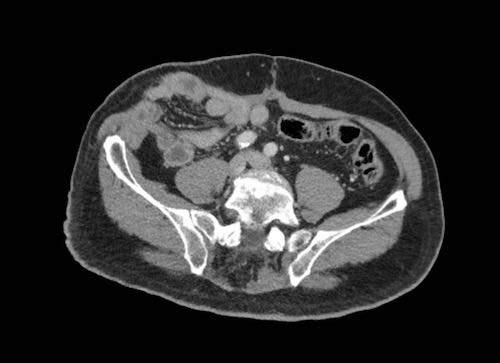

Cuộn xem ảnh CT

Ca lâm sàng 1

Cuộn qua các lát cắt.

Bạn có thể phát hiện tất cả các tổn thương cấy ghép phúc mạc không?

Bệnh nhân này đã được phẫu thuật và toàn bộ phúc mạc được ghi nhận phủ kín bởi các tổn thương u dạng kê.